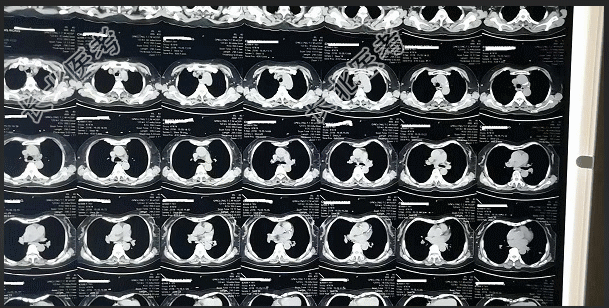

- [材料题] 【一般资料】男性,60岁,农民【主诉】咳嗽、咳痰、喘息间作7年余,加重伴发热2天。【现病史】患者缘于7年余前因着凉后出现咳嗽、咳痰、喘息等症,以后每年冬季天气变冷后发作,春季天气转暖后症状缓解,每年发作3个月以上。曾多次在当地卫生院住院治疗,诊断为“慢性支气管炎,肺气肿”,具体治疗方案不详,病情迁延不愈。自2天前起,患者患“感冒”后出现咳嗽加重,咳大量黄白色粘痰,无痰中带血。喘息,无呼吸困难,夜间能平卧,发热,体温最高达38.6℃,无寒战。在家口服“头孢氨苄片、强力枇杷露”等药物输液治疗,症状无明显减轻。为系统诊治,今入我院治疗。【既往史】体质较差,有“双侧膝关节炎”病史10余年,间断服用“尪痹胶囊”等药物治疗。否认“结核、肝炎”等传染病史,否认“糖尿病、高血压”等病史,无药物及食物过敏史,无外伤及重大手术史,预防接种史不详。【查体】T:38.2℃,P:88次/分,R:17次/分,BP:130/80/mmHg。神清,口唇略发绀,无口角歪斜,伸舌不偏,颈软无抵抗,甲状腺未触及肿大。桶状胸,两侧胸廓对称,呼吸动度一致,语颤减弱,双肺叩过清音,听诊呼吸音弱,满布哮鸣音。心率88次/分,律齐,各瓣膜听诊区未闻及病理性杂音。腹平软,无压痛,肝脾肋下未触及,移动性浊音阴性。双下肢无浮肿。四肢肌力、肌张力正常,病理征未引出。【辅助检查】肺CT:慢性支气管炎合并肺气肿,主动脉硬化。血常规:白细胞12.3×10⁹/L,中性粒细胞百分比85%。左侧膝关节片:膝关节炎。